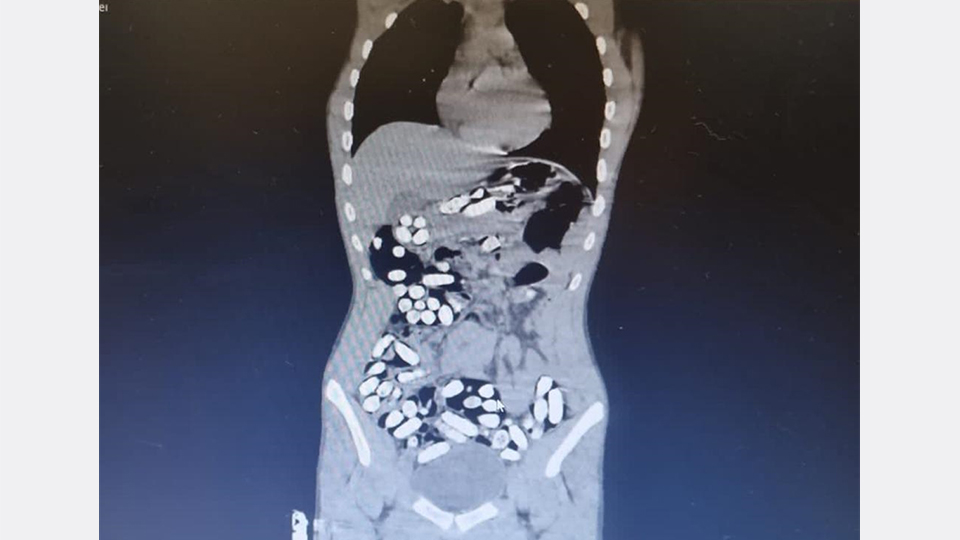

Röntgen çekimlerinde uyuşturucu kapsüllerinin şüphelilerin neredeyse iç organlarının her tarafına yayıldığı belirlendi.

Yapılan kontrollerde ve röntgen çekimlerinde, şüphelilerin vücutlarından 411 kapsül afyon sakızı olduğu belirlendi.

İlk operasyonda ve ikinci operasyonda yakalanan zanlıların, uyuşturucuları bugüne kadar rastlanılmayan "kolonoskopi" yöntemiyle vücutlarına yerleştirdikleri değerlendirildi.

Şüpheliler hastane kontrollerinde ise vücutlarına uyuşturucunun baygınken konulduğunu ve ne kadar miktarda uyuşturucunun vücutlarına doldurulduğunu bilmediklerini iddia etti.

Doktor nezaretinde 5 gün süren "dışkılama" yöntemiyle vücutlarından 6 kilo 955 gram ağırlığında 683 kapsül uyuşturucu çıkartılan 5 şüpheli, emniyete götürüldü.